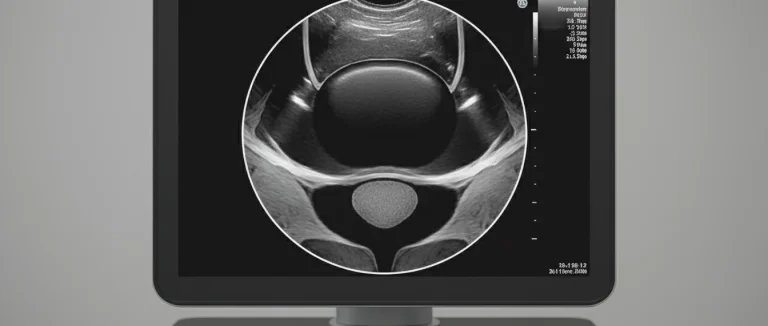

| УЗИ брюшной полости и простаты | Оценка размеров и структуры органов | Увеличение простаты, наличие камней, опухолей |

В зависимости от результатов врач может дополнительно назначить мочевую культуру, исследование функции почек (креатинин, eGFR) или нейрологические тесты. Современные центры, такие как Лив Хоспитал, используют передовые методы визуализации (MRI, CT) для точного определения локализации патологии.